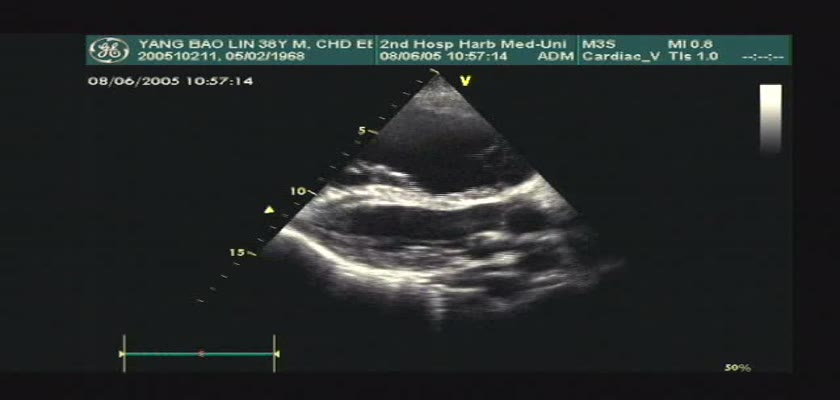

先天性心脏病超声诊断-先天性心脏病超声诊断视频20